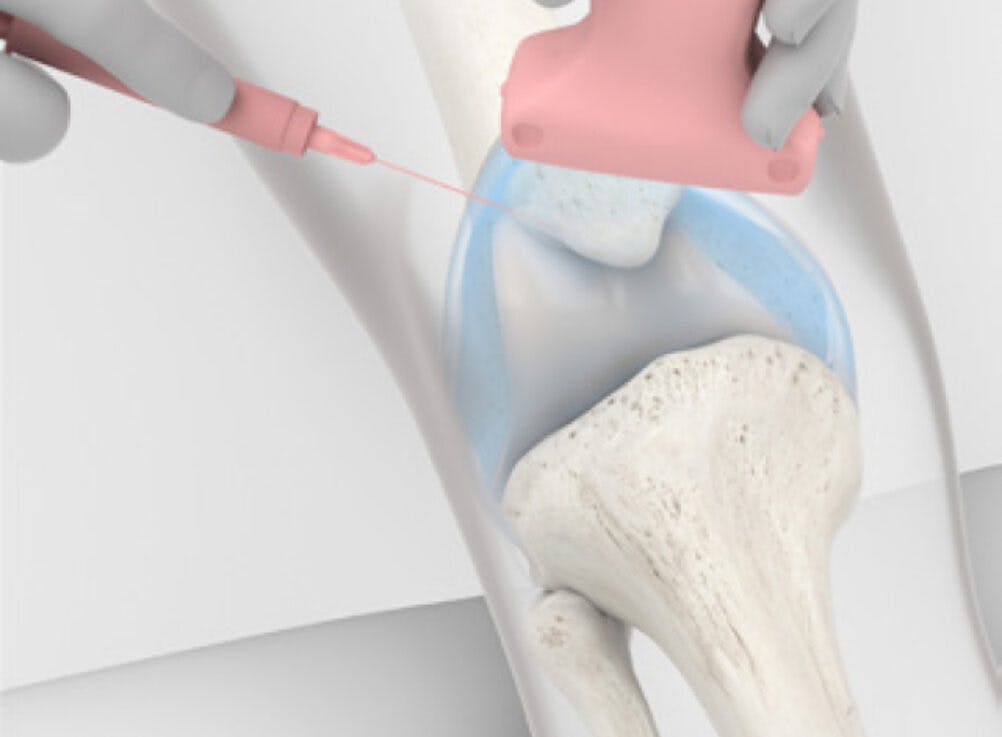

Osteoartróza, bolestivé ochorenie, pri ktorom sa kosť trie o kosť v dôsledku degradácie chrupavky, postihuje podľa Svetovej zdravotníckej organizácie viac ako 500 miliónov ľudí na celom svete, pričom najčastejšie postihnutým kĺbom je koleno. Operácie nie vždy prinášajú želané výsledky a dospelí majú zvyčajne problém s regeneráciou stratenej chrupavky. Vedci z Connecticutskej univerzity teraz dosiahli významný prelom, ktorý ponúka nádej pacientom s osteoartrózou na celom svete. Ich gélová injekcia by mohla zabezpečiť nápravu bez chirurgického zákroku.

Pri osteoartróze sa postupne zmenšuje ochranná chrupavka v našich kĺboch. Keď sa úplne opotrebuje, chorí trpia neznesiteľnou bolesťou a majú obmedzenú pohyblivosť. Nový objav prináša neinvazívne riešenie na regeneráciu poškodenej chrupavky. Biomedicínski inžinieri pracujú na lešeniach kompatibilných s ľudskou chrupavkou, ktoré môžu stimulovať opätovný rast, keď sa implantujú do kolena. Aj tieto regeneračné riešenia si však vyžadujú invazí ...